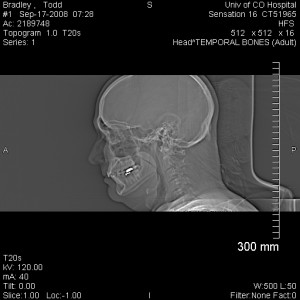

Todd in profile as seen by the CT scan Today I took the day off work for a couple reasons. First, my parents needed someone to take them to the airport at an ungodly hour. I got up at 4:26 AM in order to drop them off at 5:45 AM, so they could catch a plane for Africa.

So I decided that since I was going to be in the vicinity, I might as well schedule my head CT for this morning and just do that on the way back from the airport. So at 7:00 AM I had the head CT, and then at 8:45 AM, I had an appointment with my ear doctor to look over the results.